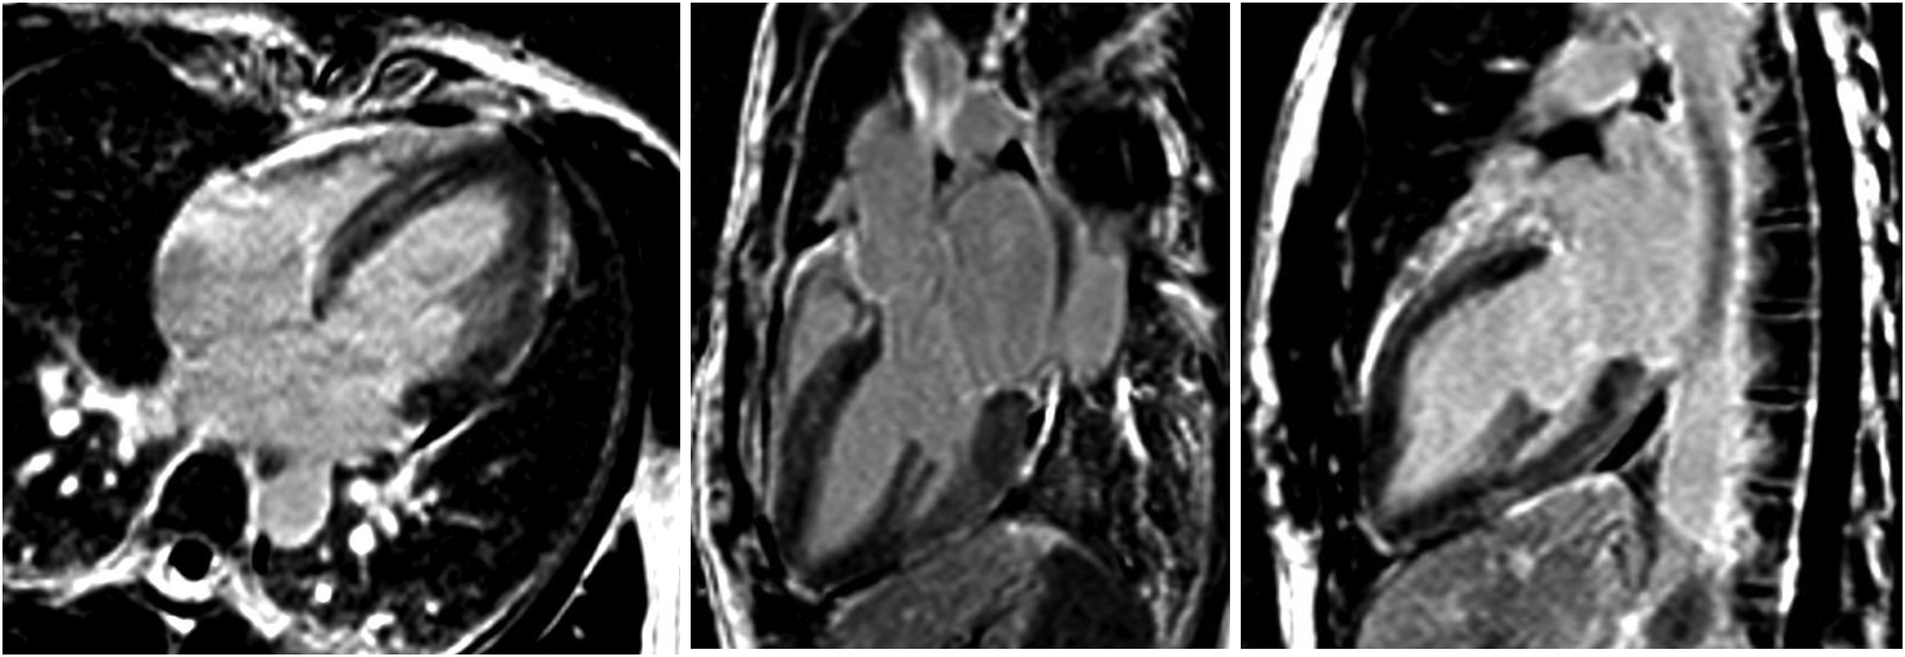

A subsequent TTE on day ten showed normalization of the LVEF to 63%, as well as the disappearance of the segmental wall motion abnormalities. The patient was discharged on day twelve without any treatment. Because of a rapid full cardiac function recovery, the hypothesis of an inflammatory cardiomyopathy as well as spontaneous coronary artery dissection was ruled out, confirmed by the follow-up cardiac MRI performed at three months, which showed the complete resolution of ventricular dysfunction. All these elements were in favor of a final diagnosis of reverse TTS triggered by brainstem lesions of MS (Figure 5: absence of irreversible tissue injury (late gadolinium enhancement) in four, three and two-chamber views) (16).

Figure 5

Absence of irreversible tissue injury (late gadolinium enhancement) in four, three and two-chamber views.